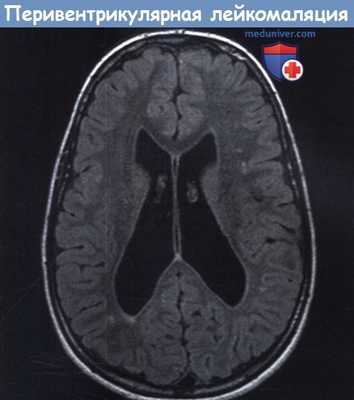

![Признаки энцефалопатии Вернике на снимке МРТ [22]](/pimg3/narushenie-zreniya-pri-CFCD4.jpeg)

Может применяться компьютерная томография (КТ) и магнитно-резонансная томография (МРТ). С помощью КТ определяют участки пониженной плотности в центральном сером веществе среднего мозга и в части таламуса, но в большинстве случаев этот метод не выявляет очаговой патологии при острой энцефалопатии.

Наиболее эффективный метод диагностики энцефалопатии Вернике — это МРТ. Интерпретировать результаты МРТ сможет только врач.